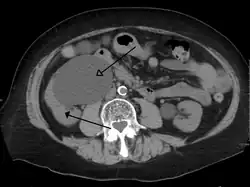

-

CT scan of bilateral hydronephrosis due to a bladder cancer -